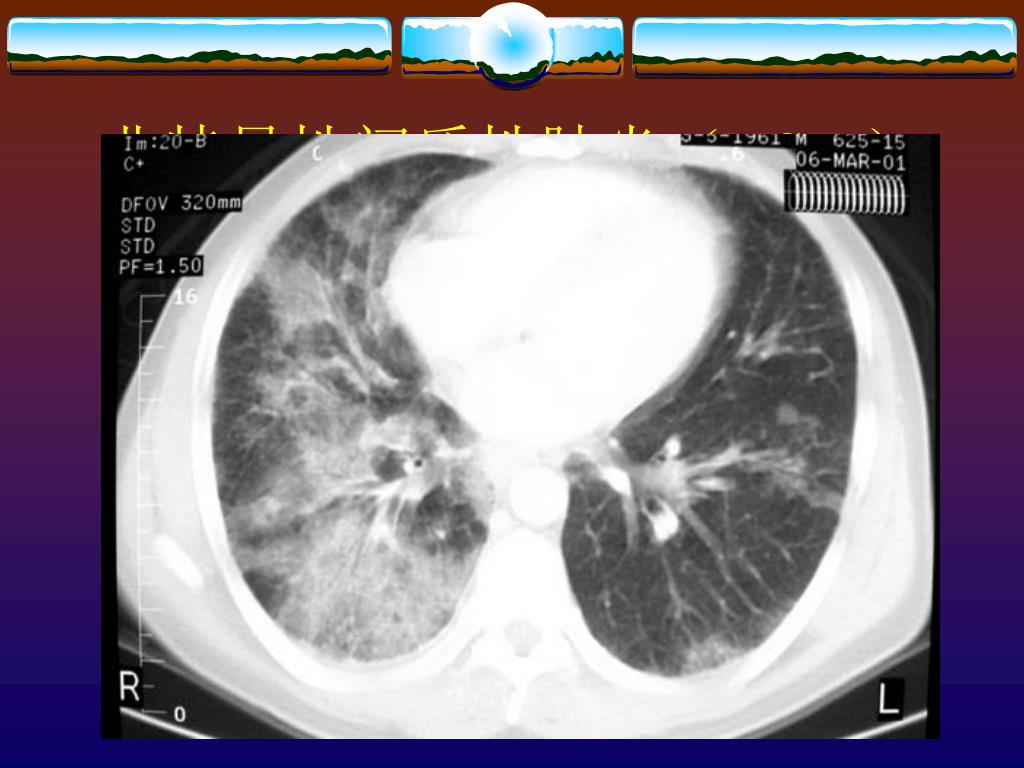

16. 非特异性间质性肺炎(NSIP)